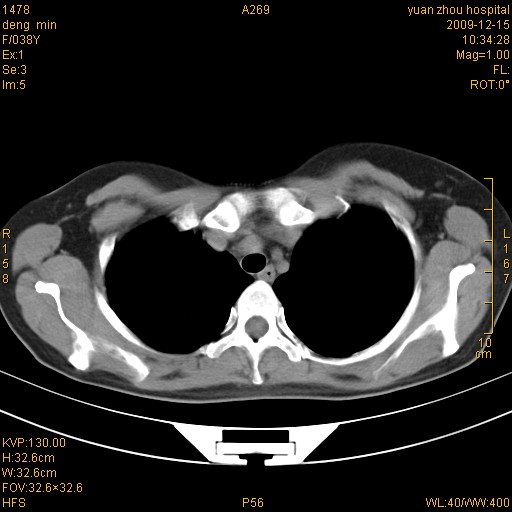

标题: CT23919:F38Y 咳嗽月余 [打印本页]

标题: CT23919:F38Y 咳嗽月余